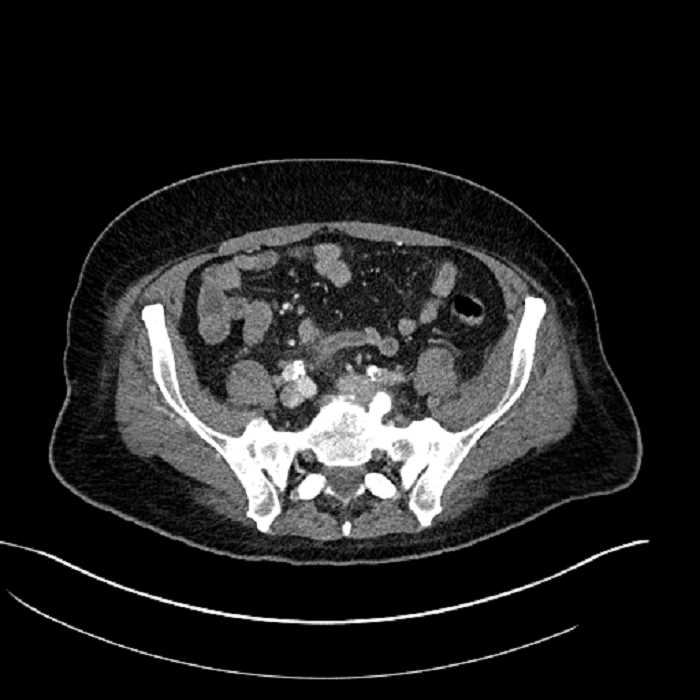

• Mild mural thickening of a segment of the sigmoid colon with adjacent fat stranding and a 1.5 cm fluid and gas collection along the tip of an inflamed diverticulum

• Loss of the normal fat plane between this collection and adjacent loops of small bowel, which demonstrate mural thickening

• High grade stenosis of the left common iliac artery, with the left internal and external iliac arteries remaining patent

• Ankylosis of both sacroiliac joints

Acute sigmoid diverticulitis complicated by a small contained perforation and a large abscess in the right hepatic lobe. Additional small subcapsular abscesses along the anterior margin of the left hepatic lobe.

Additionally, loss of the normal fat plane between the peridiverticular collection and adjacent thickened loops of small bowel raises the potential for an enterocolonic fistula.

High grade stenosis of the left common iliac artery. The left external and internal iliac arteries are patent.